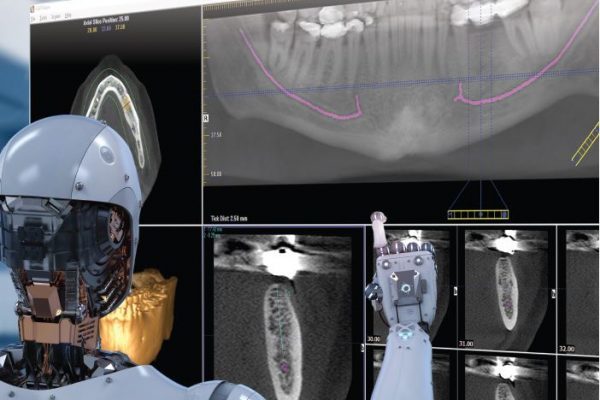

Artificial intelligence software traced a perfect ID nerve in 4.5 seconds

Artificial intelligence (AI) in dentistry is dedicated to teaching computers how to automate radiological diagnostics using deep learning. Its…

Dentistry